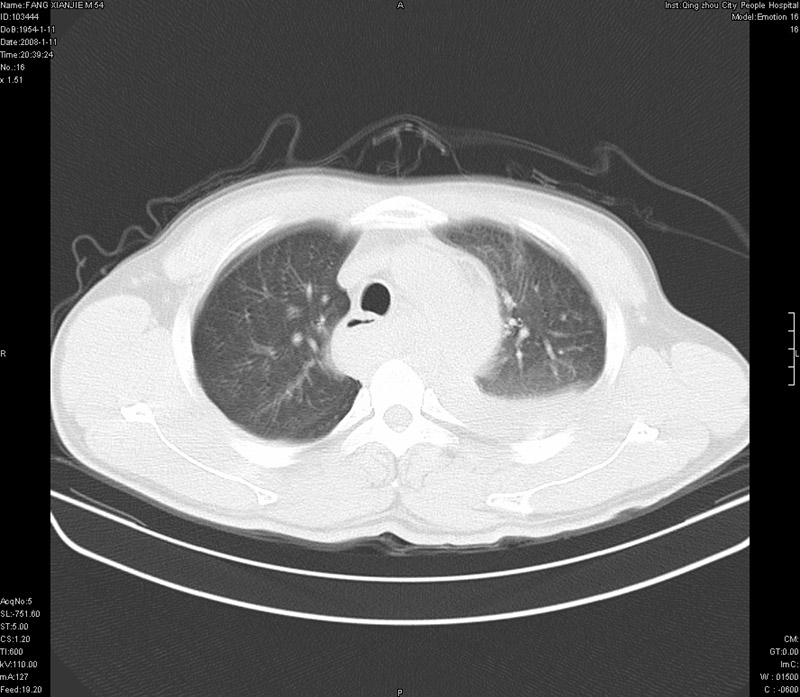

男性,40岁。胸部被车压伤伴胸痛1小时来院就诊。检查:一般情况尚可,血压110/80,胸部及上腹部压痛。结果在三天后公布。骨窗在横断位、冠矢状显示肋骨、胸椎、和胸骨未见骨折征象。

ct11308:胸部外伤1小时(证实病例) (2008-1-13 16:2)结果如下:病人入院后两小时后症状加重,8小时后在征得病人家属同意做了ct增强扫描。如下图。最终临床诊断:外伤性胸主动脉破裂并纵隔内血肿。由于有运动性伪影,胸骨在矢状面重建的图像似有骨折征,这是一种假象,我们称之为“假骨折”,这在多层ct重建中经常性遇到,必要时要结合横断图像鉴别之。现在,病人的一般情况较差,是否要手术家属尚有争议,如果手术修补,难度较大,需要专门预定制作固定支架。

当然,对于该病例,其它非重要的诊断还有:右侧少量气胸;左侧胸腔积液;左侧轻度肺挫裂伤。对于纵隔内血肿,我们曾经遇到过多例,也有怀疑主动脉的破裂,但是,均未得到具体出血部位的明确诊断。